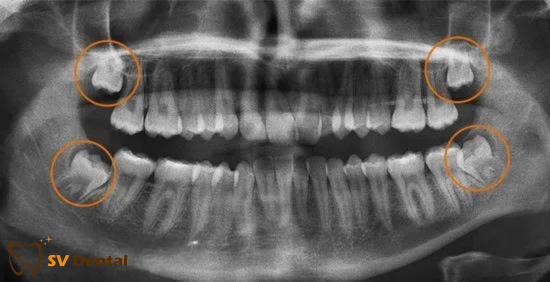

Răng khôn, hay còn gọi là răng số 8, là 4 răng hàm nằm trong cùng mỗi cung hàm. Răng khôn thường bắt đầu mọc trong độ tuổi 18 – 25 tuổi.

Do mọc muộn khi xương hàm đã phát triển gần như hoàn chỉnh, đa số răng khôn không đủ không gian để mọc thẳng. Vì thế, răng khôn thường bị:

Răng khôn có thể mọc kẹt theo nhiều dạng khác nhau:

Mỗi trường hợp có mức độ khó – dễ khác nhau, đòi hỏi bác sĩ phải chẩn đoán kỹ bằng phim X-quang hoặc CT cone beam trước khi tiến hành xử lý.